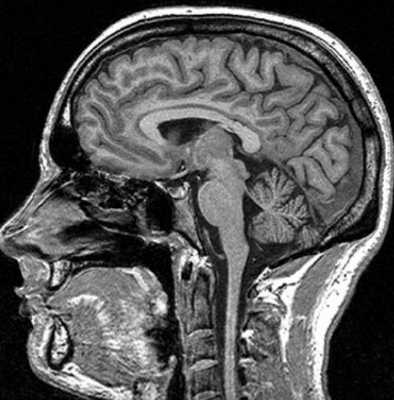

МРТ костей черепа что показывает

Магнитно-резонансная томография базируется на способности магнитного поля изменять состояние атомов водорода в молекулах воды. Процедура информативна относительно мягких тканей, насыщенных жидкостью. Структуры организма с низким содержанием воды на снимках отражаются плохо. МР-томограф фактически «не видит» костную ткань. По этой причине рутинная диагностика переломов включает рентгенографию и КТ (в экстренных, спорных либо сложных ситуациях). При травмах головы стандартное обследование с помощью Х-лучей нередко сочетают с магнитно-резонансной томографией. В зависимости от того, что показывает МРТ костей черепа, дополняют тактику лечения, основанную на результатах КТ. Процедура дает информацию о состоянии мягких структур и влиянии на последние травм.

Показывает ли МРТ перелом черепа?

Диагностическая ценность магнитно-резонансной томографии высока при травмах сложных структур организма (черепная коробка, позвоночник, сочленения). По результатам сканирования диагностируют не сам перелом, а сопутствующие повреждения (разрывы связок, мышц, компрессию тканей и пр.).

На вопрос «Показывает ли МРТ перелом черепа?», врачи дают отрицательный ответ. При травмах головы методом выбора является компьютерная томография. По снимкам оценивают состояние костей, обнаруживают малейшие повреждения последних, кровотечения. Компьютерная томография особенно информативна в первые 48 часов после получения травмы. В дальнейшем изменения в мозге контролируют посредством МР-сканирования.